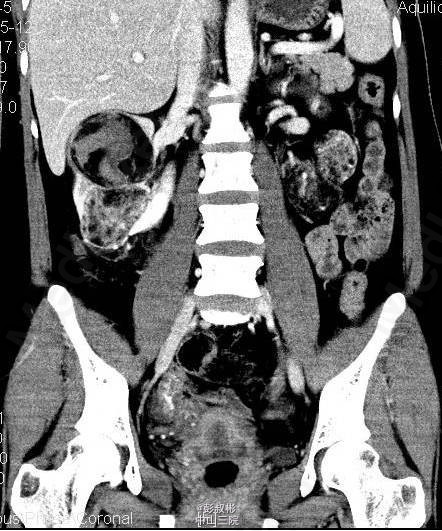

3、既往史:无特殊 4、体格检查:双肾区无红肿、隆起,左肾区叩击痛(-),右肾区叩击痛(+),左侧肋脊点、肋腰点压痛(-),右侧肋脊点、肋腰点压痛(+)。腹平软,左侧输尿管走行区压痛(-),右侧输尿管走行区压痛(-),膀胱区无膨隆,压痛阴性。 5、辅助检查:尿常规:白细胞计数27.60个/ul; 生化全套:钾3.290mmol/L;血常规:白细胞总数12.730x10E9/L,中性粒细胞绝对值9.950x10E9/L心电图、胸片正常;肿瘤抗原检查正常。ECT:右肾灌注、功能轻度降低;左肾灌注、功能基本正常。GFR:左肾为67.3ml/min,右肾为30.6ml/min。CTU:右肾体积增大,双肾可见多发大小不等结节状、团块状异常密度影,其内密度欠均匀,病灶内可见脂肪密度影,增强扫描呈不均匀强化,最大者位于右肾,约59×54mm,双肾多发错构瘤,右肾错构瘤出血。

6、入院诊断:双肾错构瘤(右肾肿物破裂出血可能) 7、处理:予心电监护、吸氧、留置尿管,引流出淡黄色尿液1600mL;急查血常规、生化未见明显异常;予抗感染、补液及营养支持治疗。拟行腹腔镜下右肾部分切除术,备右肾切除术。